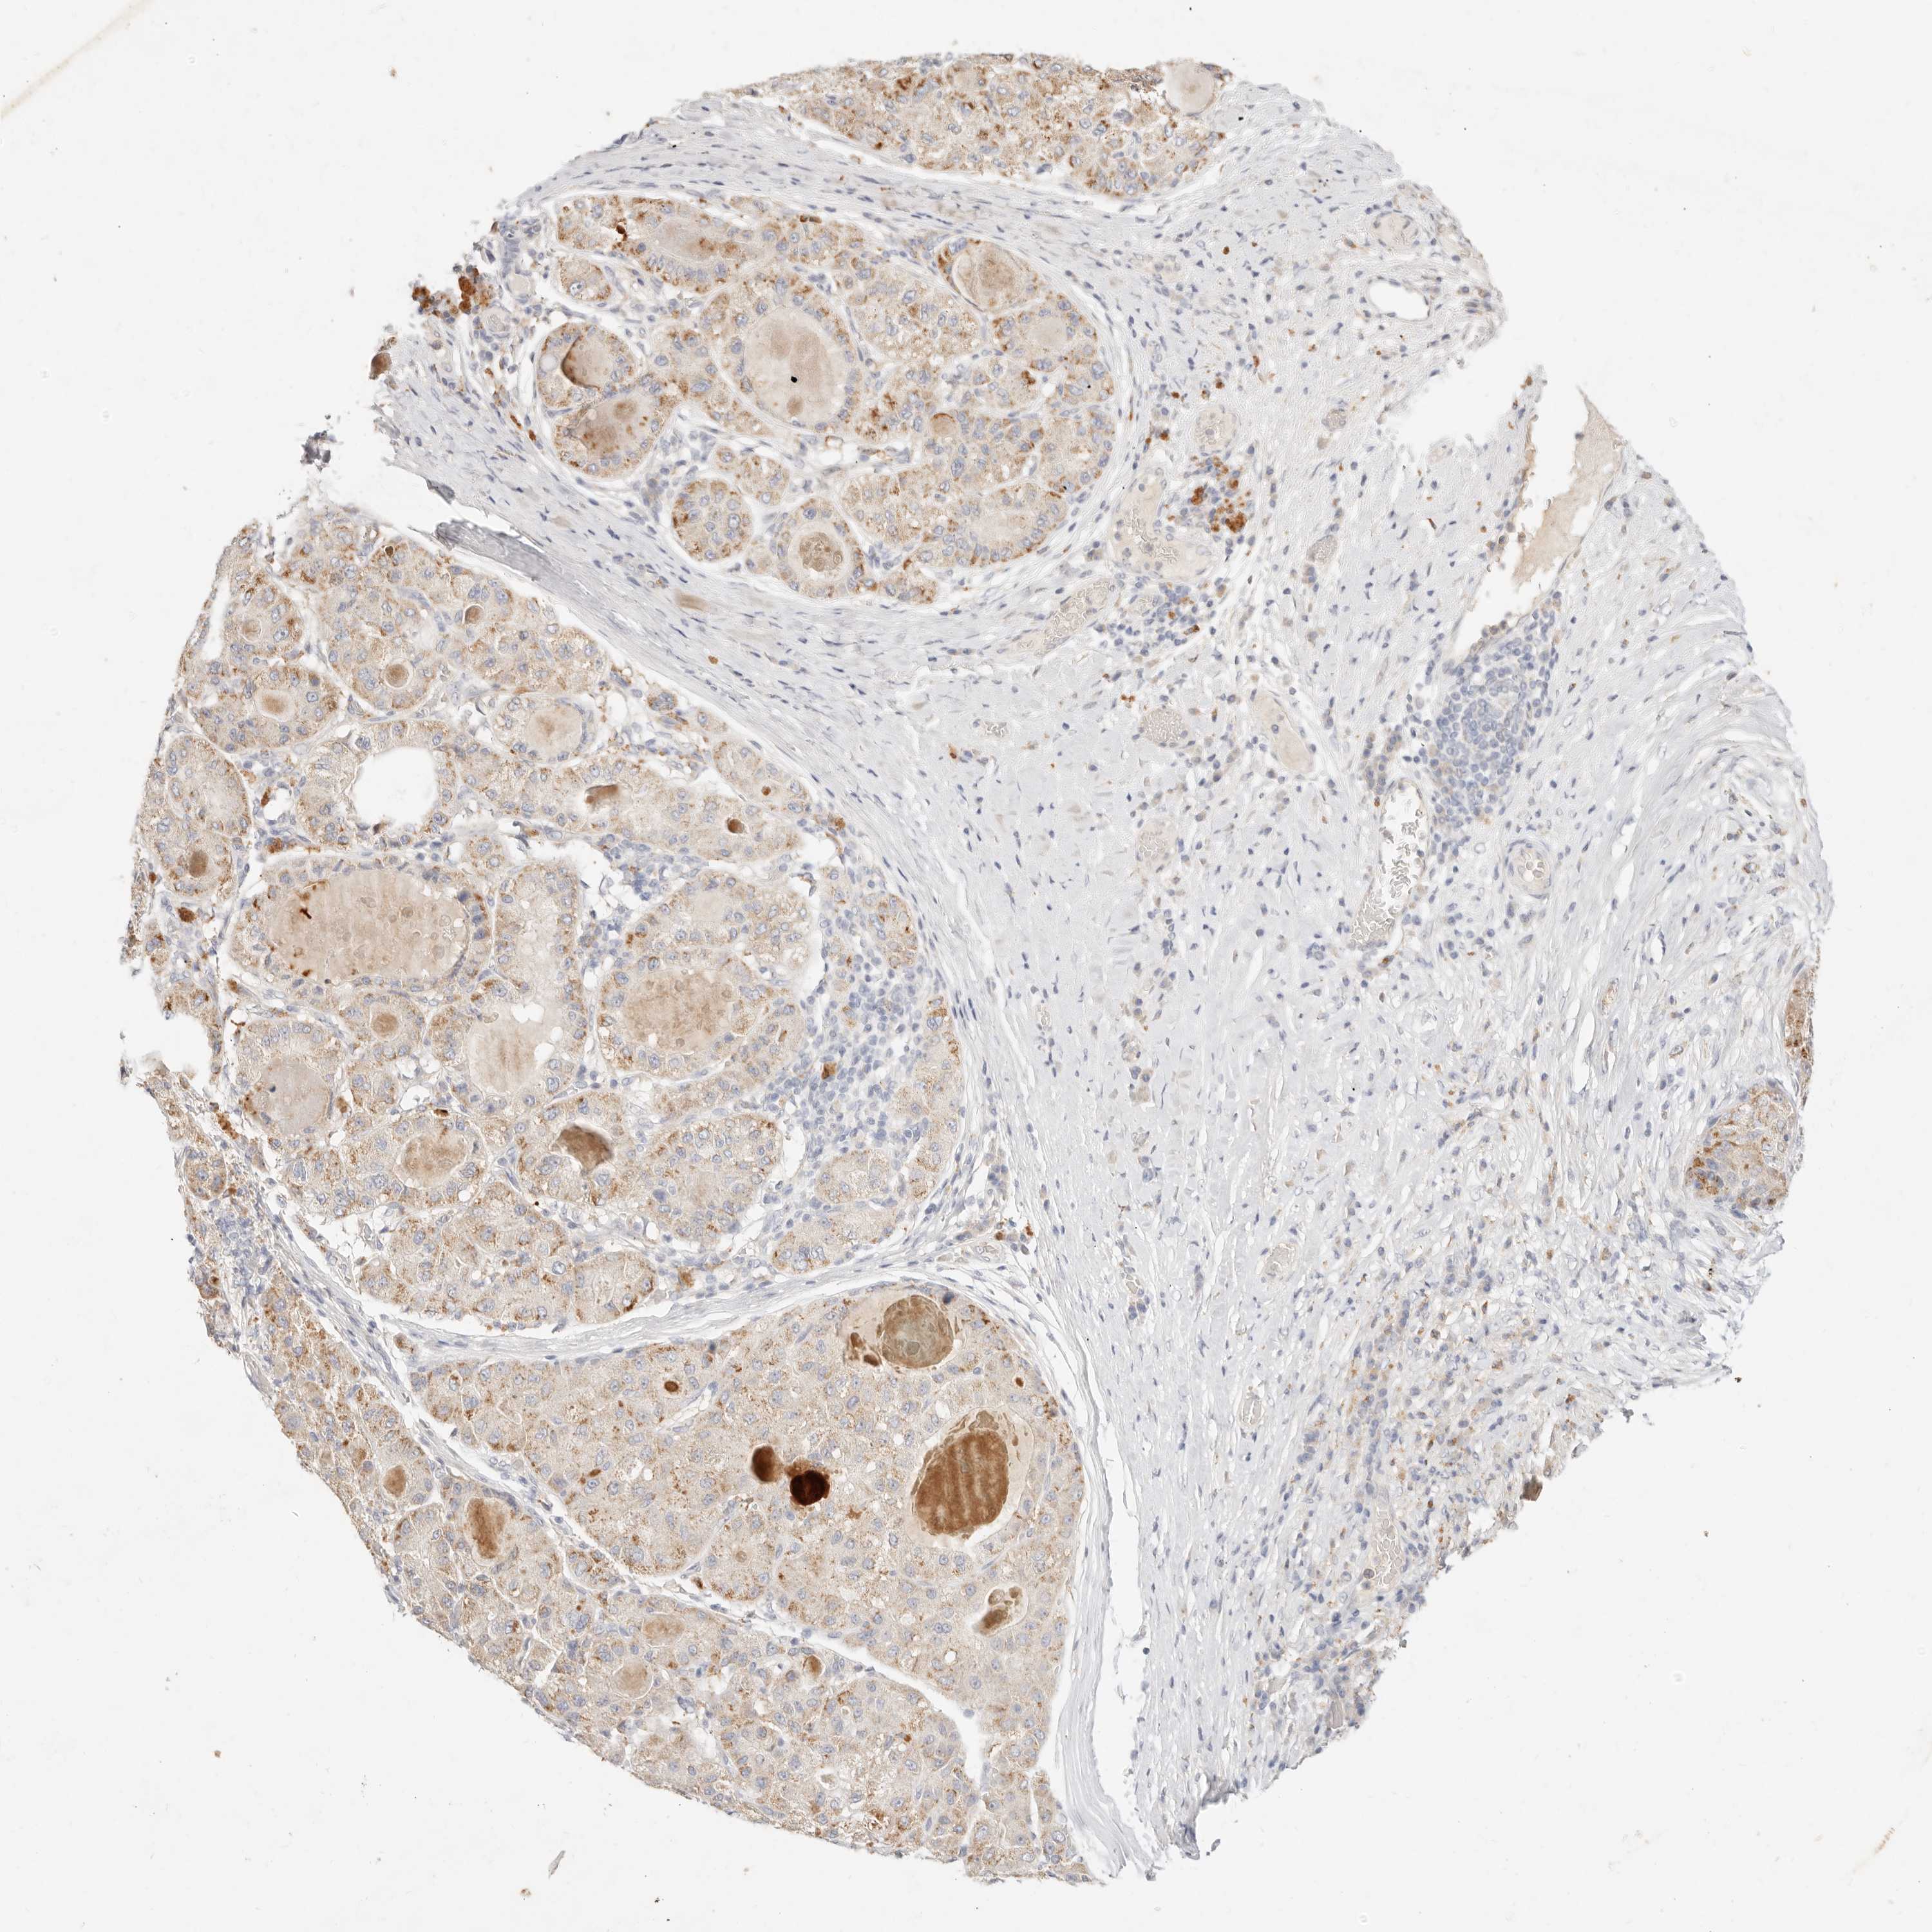

LIVER CANCER - Protein expressioni

A mouse-over function shows sample information and annotation data. Click on an image to view it in a full screen mode. Samples can be filtered based on level of antibody staining by selecting one or several of the following categories: high, medium, low and not detected. The assay and annotation is described here.

Note that samples used for immunohistochemistry by the Human Protein Atlas do not correspond to samples in the TCGA dataset.

Antibody stainingi

Antibody staining in the annotated cell types in the current human tissue is reported as not detected, low, medium, or high, based on conventional immunohistochemistry profiling in selected tissues. This score is based on the combination of the staining intensity and fraction of stained cells.

Each image is clickable and will lead to virtual microscopy that enables deeper exploration of all samples and also displays staining intensity scores, fraction scores and subcellular localization as well as patient and tissue information for each sample.

Antibody HPA021192

Antibody HPA021195

Antibody HPA028759

Antibody CAB021094

Staining

High

Medium

Low

Not detected

Intensity

Strong

Moderate

Weak

Negative

Quantity

>75%

75%-25%

<25%

None

Location

Nuclear

Cytoplasmic/membranous

Cytoplasmic/membranous,nuclear

Cholangiocarcinoma

Carcinoma, Hepatocellular, NOS